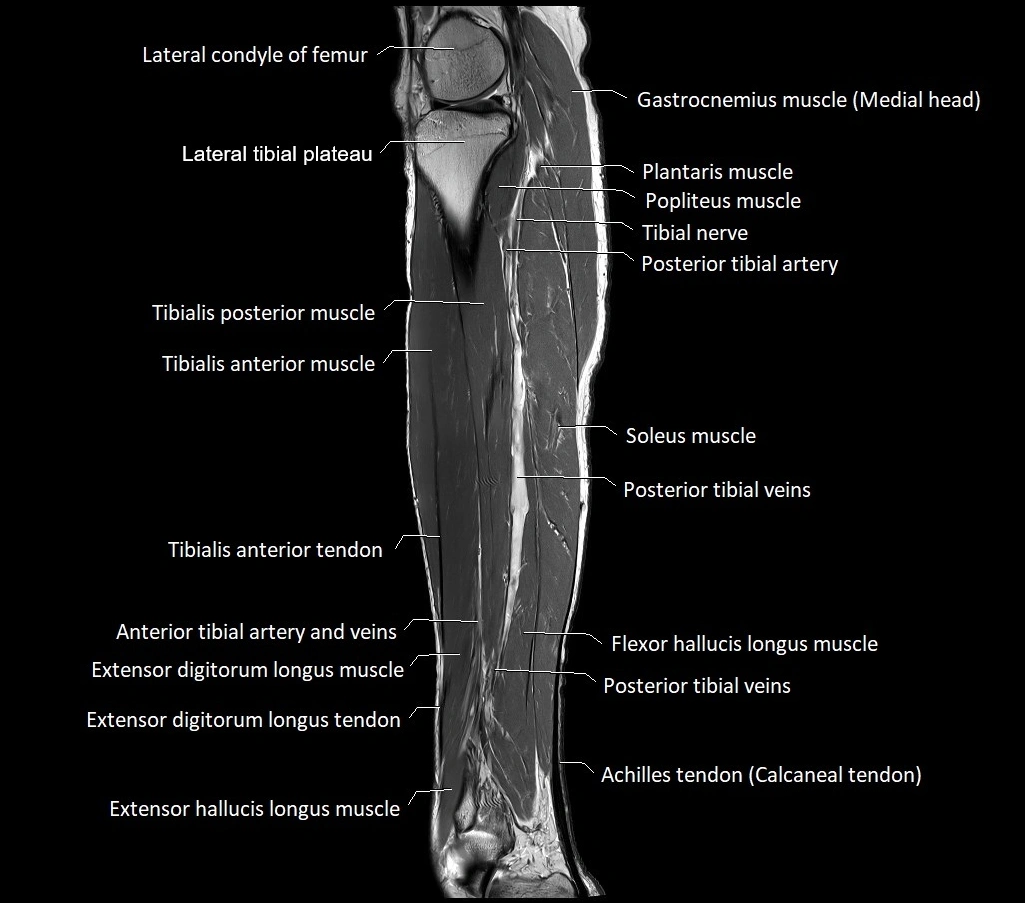

MRI image